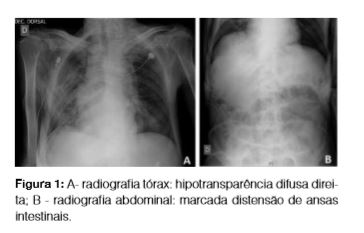

Ao quinto dia de internamento apresentou vómitos escuros, queda de 3 g de hemoglobina e aumento dos parâmetros inflamatórios. A radiografia do tórax (Fig 1-A) mostrou provável pneumonia de aspiração secundária aos vómitos. Tinha ainda distensão de ansas intestinais visível em radiografia abdominal (Fig. 1-B), endoscopia digestiva alta relevou (Fig 2 A,B e C) esófago negro com mucosa circunferencialmente ulcerada, negra, sugestiva de isquemia, aspectos que se interrompem abruptamente ao nível da transição esofagogástrica; aparente ausência de motilidade gástrica. Não foi realizada biópsia esofágica pelo evidente risco de perfuração. Instituído jejum, inibidor da bomba de protões e fluidoterapia, melhorando. Re-introduzida a alimentação progressivamente, com sucesso. Teve alta ao 21º dia de internamento. Três meses depois a endoscopia de reavaliação mostrou mucosa esofágica completamente normal e sem estenoses (Fig 2-D).